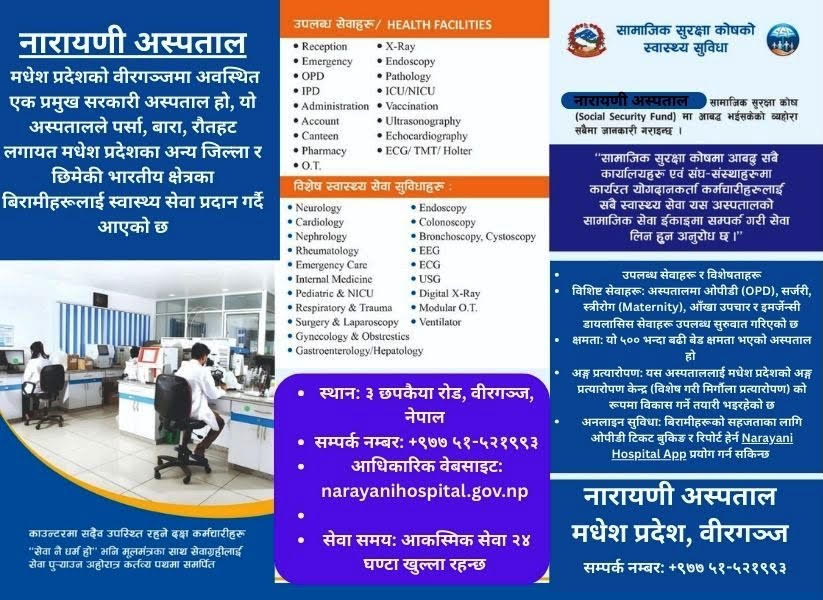

सो सेन्टरले विगत १० वर्षदेखि काठमाडौंको रातोपुलगायत देशका आठ ठाउँ (ललितपुको पुल्चोक, भक्तपुरको टेखापुखु, मुस्ताङचोक पोखरा, झापाको शनिश्चरे रोड, बुटवलको सुख्खा नगर, दाङको तुलसीपुर र चितवनको भरतपुर) मा बाथरोग सेन्टर सञ्चालन गरेर बाथरोगको प्रभावकारी उपचार सेवा उपलब्ध गराउँदै आएको सेन्टरका प्रबन्ध निर्देशक रोशन कक्षपतिले बताए ।